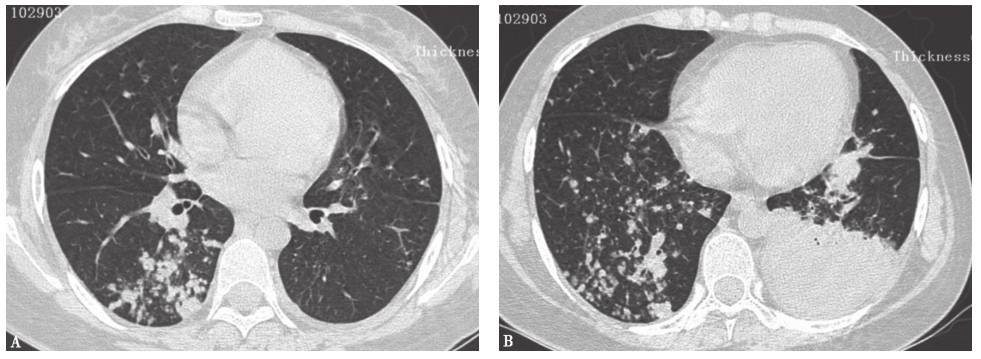

17个月前胸部CT见双肺弥漫性小结节(图1)。

图1 17个月前胸部CT表现